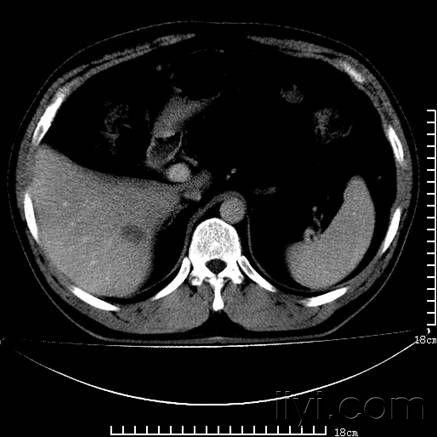

请大家分析肝脏低密度影

图片尺寸437x437